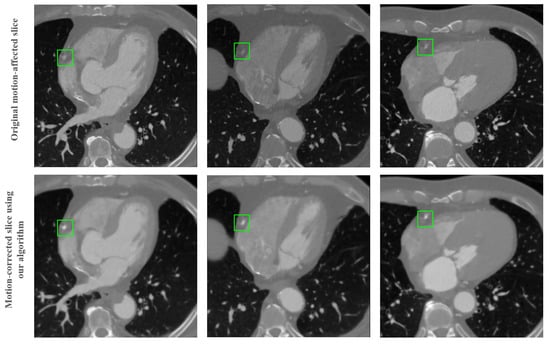

Figure 10 illustrates the efficacy of our proposed motion correction algorithm, especially highlighting the seamless integration of 2D-patch-based corrections back into the 3D CT volume. The upper row of the figure displays original slices from the CT volume that were previously affected by motion artifacts. Notably, these slices include the right coronary artery (RCA), a region typically susceptible to motion-induced distortions.

Figure 10.

Comparison of axial views of a CT volume before and after applying the proposed coronary motion correction algorithm including re-insertion and volumetric interpolation. The upper row shows the original motion-affected slice and the lower shows the slice after motion correction using our algorithm. The RCA region is highlighted with green boxes.

Following the application of our motion correction algorithm on these 2D patches, we reinserted them into the original 3D volume. The lower row of the figure showcases these post-correction slices. It is particularly remarkable to observe how the reinserted patches blend seamlessly with the surrounding areas, with no discernible artifacts or discontinuities. This seamless integration is further enhanced by the volumetric interpolation technique we employed, ensuring that the corrected patches maintain spatial and anatomical consistency with the adjacent uncorrected regions.

The RCA region, highlighted with green boxes in both rows, serves as a clear point of comparison. In the corrected slices, one can observe a marked reduction in motion artifacts, resulting in clearer and more defined images of the coronary artery. This comparison not only validates the effectiveness of our motion correction approach but also demonstrates our algorithm’s capability to maintain the integrity and continuity of the 3D structure in the CT volume.